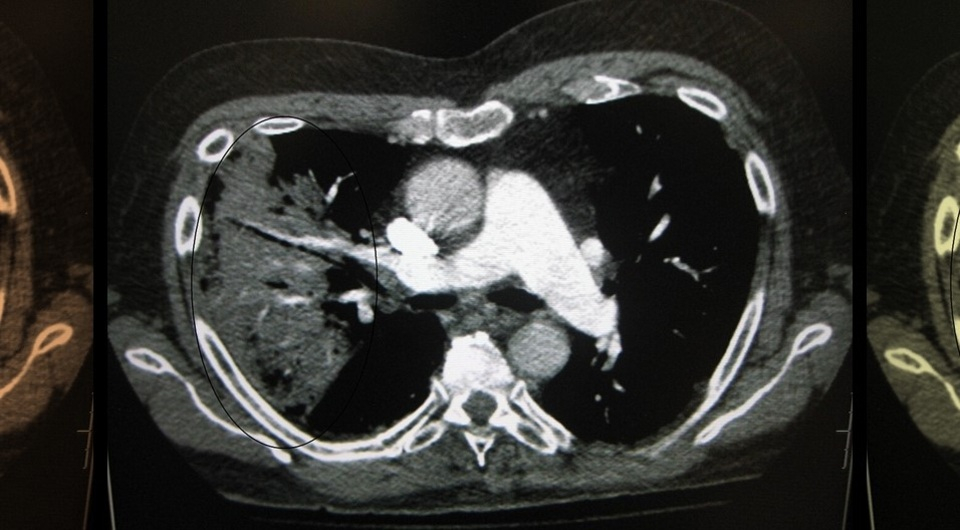

Стивен Николлс (Stephen Nicholls) из Университета Монаша с коллегами из шести стран провели вторичный анализ данных клинических испытаний и обнаружили, что прием агониста глюкагоноподобного пептида-1 семаглутида уменьшает число и продолжительность госпитализаций у пациентов с избытком массы тела или ожирением и сердечно-сосудистыми заболеваниями.

В работе использовали данные всех 17604 участников (медианный возраст 61 год; 27,7 процента — женщины) международных рандомизированных контролируемых испытаний третьей фазы SELECT. Все они имели индекс массы тела 27 и более килограмм на метр в квадрате и диагноз серд